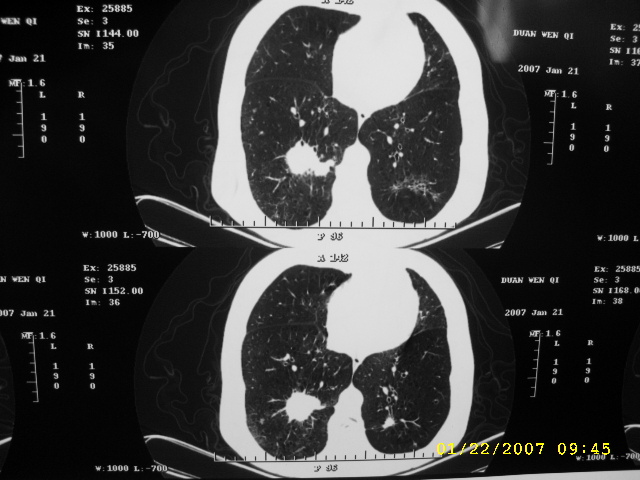

女,75.胸痛。

07.01.21.

明显的不规则形肿块,分叶、短毛刺、胸膜刺激征,血管扭曲征等周围型肺癌的征象明显,应首先考虑周围型肺癌。应与肺多发结核球相鉴别

双侧肺内块状病灶,均见分叶毛刺,左肺见典型胸膜凹陷,双侧双原发癌.

1.双肺上叶及右肺下叶结节,周围散在卫星灶,接近4年的病史,纵隔无肿大淋巴结,考虑结核

2.桶状胸,慢支,肺气肿